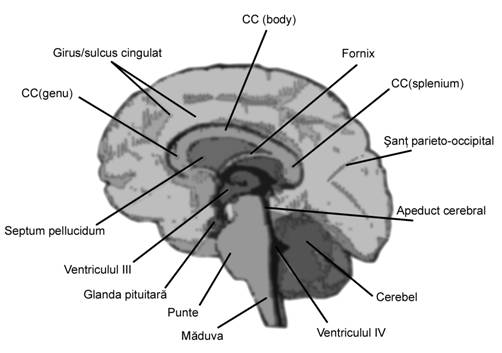

Fig. nr. 156 Planurile de sectiune sagitale craniene (adaptat dupa [8] si [14] )

Fig. nr. 157 Planul VIII de sectiune sagitala prin creierul fetal pune in evidenta : 1 cortex cerebral, 2 corpus calosum, 3 cavum septi pellucidi ,4 talamus cu ventricul III,

5 lamina tecti, 6 glanda hipofiza , 7 puntea, 8 bulbul ( medulla oblongata ), 9 cerebellum, 10 cisterna magna . ( adaptat dupa England [5] ).

Planul VIII defineste profilul fetal in pozitie occipitoposterioara. Profilul de-vine vizibil de la sfarsitul trim I. In aceasta sectiune se pot oserva miscarile fiziologice fetale de deschidere a gurii, miscarea limbii, inghitirea, aspiratia de lichid amniotic.

Pozitia favorabila fetala poate pune in evidenta cavum septum pellucidi, corpus calosum (dupa 20 de sapt), lamina tecti, pons sau cerebellum.

Fig. nr. 162. Schita anatomica a creierului in sectiune sagitala. (adaptat dupa Pooh in [7])